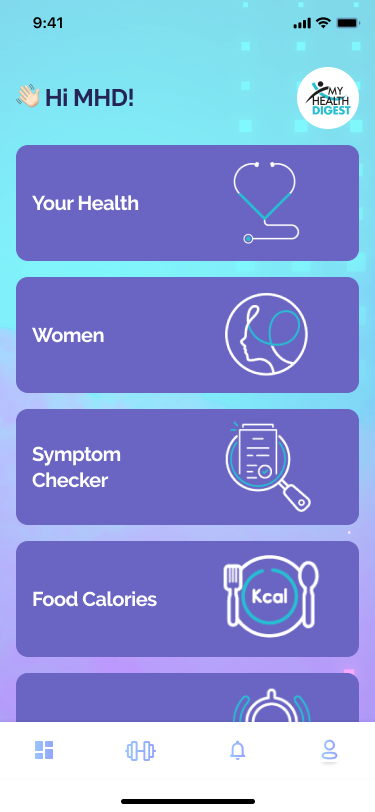

First patient education materials to deliver up-to-date information on health, disease prevention and treatment options to patients, workers and the general public.

All our products (booklets, brochures, posters, visuals, and interactive software) have complete & approved medical information, appealing design and accurate up-to-date medical art and text.

We reach people through all possible channels to deliver the best education possible to live long, prosperous & healthy life.